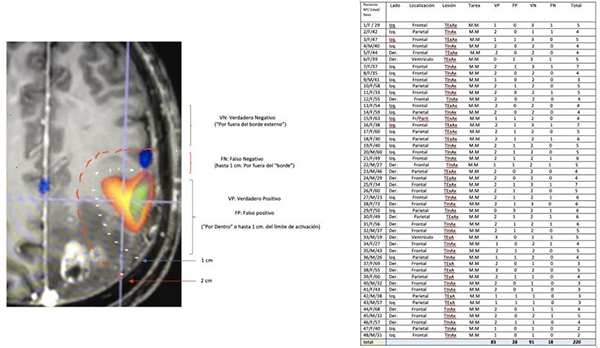

Las respuestas de las áreas de cada sticker se distribuyeron en una tabla estadística de 2 x 2, metodología que nos permitió el análisis de los resultados quirúrgicos.

Se utilizó un test binario (tabla 2 x 2) para validar la respuesta motora en el área de activación de la RMfm. El test de referencia para validar la prueba fue la electroestimulación cortical directa (ECD).

Las respuestas a la ECD (Estimulación Cortical Directa) se clasificaron en este trabajo como: 1 (VP): verdadero positivo: cuando se observa respuesta motora por ECD dentro del área de activación de la RMfm, o hasta un máximo de 1 cm por afuera del “borde”, 2 (VN): verdadero negativo cuando hubo ausencia de respuesta por fuera del “borde” del área de activación de la RMfm, (3)FP: falso positivo ausencia de respuesta motora por ECD dentro del área de activación de la RMfm (ó su borde), 4: falso negativo la presencia de respuesta motora por ECD 1 cm por fuera del “borde del área de activación BOLD.

Resultados de la prueba (Tabla Nº1)

Se realizaron un total de 220 (tabla Nº2) registros luego las respuestas se distribuyeron para su análisis estadístico en una tabla 2 x 2 (tabla N° 3):

La tabla de contingencia nos permitió determinar los siguientes resultados estadísticos: P (prevalencia), S (sensibilidad), E (especificidad), VP+ (Valor Predictivo positivo del test), VP – (Valor Predictivo negativo del test), LR + (Likelihood Ratio positivo), LR – (Likelihood Ratio negativo), Odds pre-test, Odds post test (+), Odds post test (-).